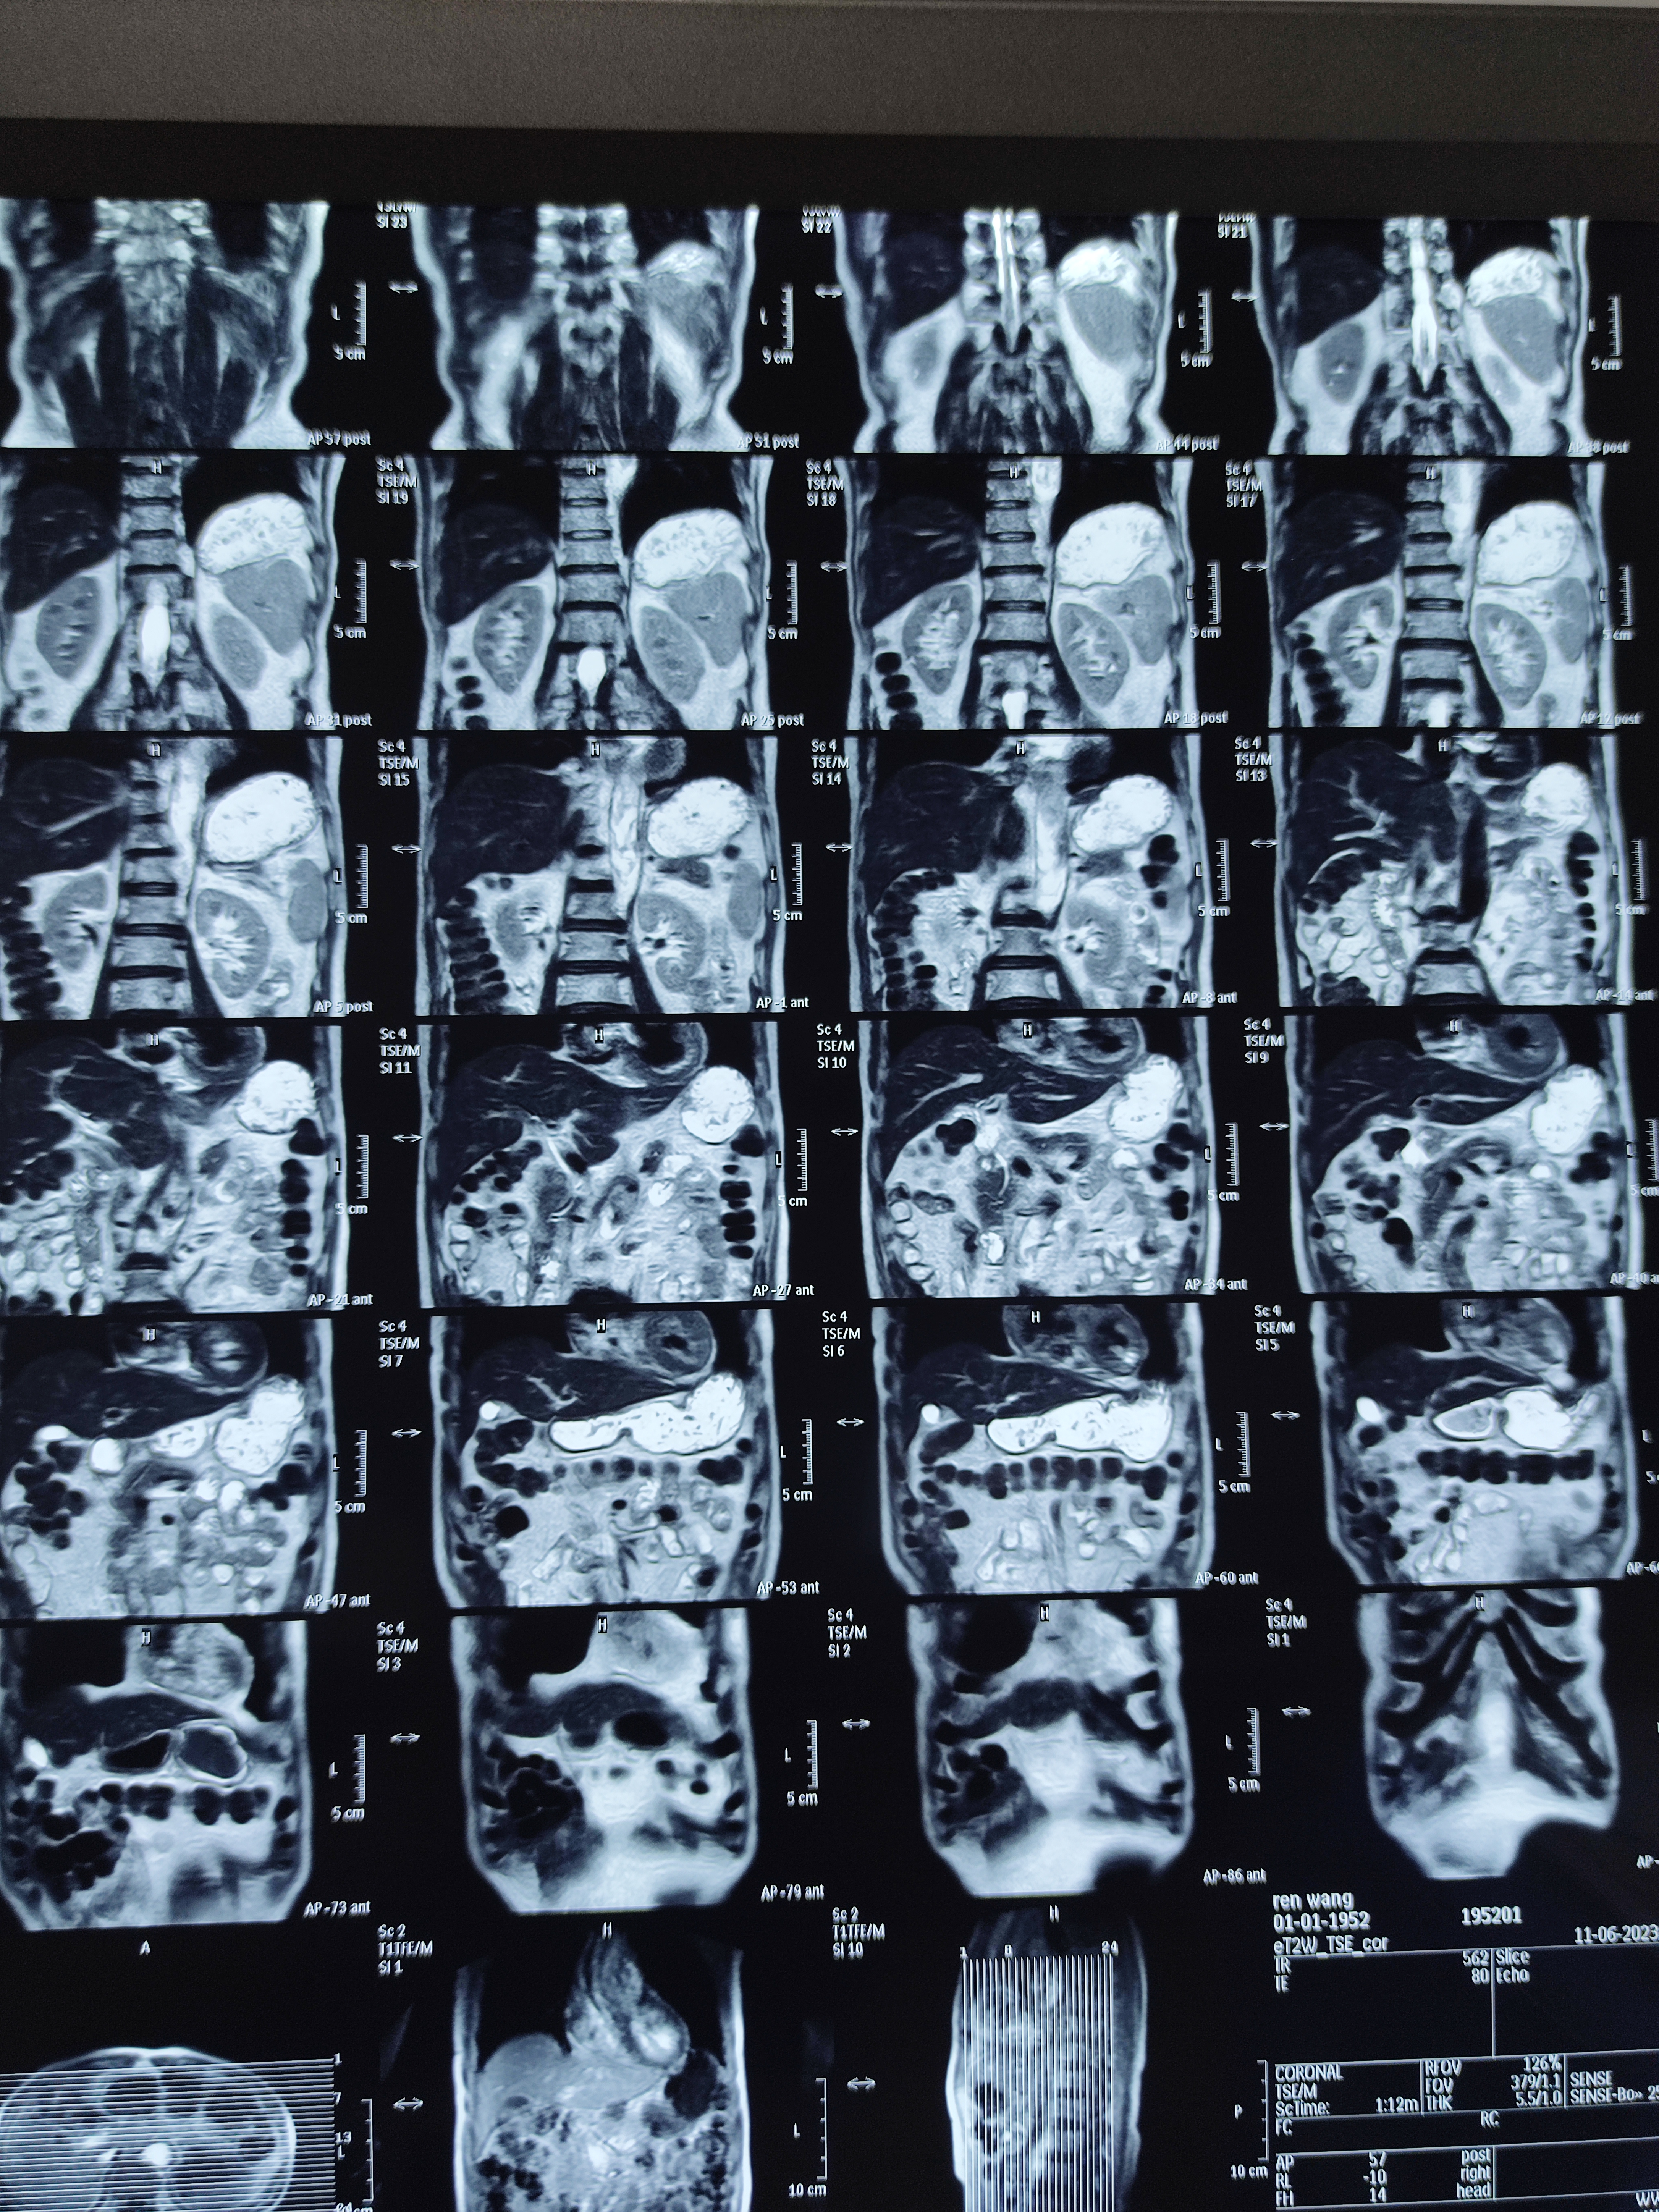

四月份癌胚抗原还是5.6,这个月到8了,持续升高。做了核磁增强,左侧桥小脑角哪有个地方不确定。肝脏核磁平扫弥散有两个点状高信号,转移也排不了,胃肠镜正常,左颈部有个变圆的淋巴结,保险点是不该加个化疗药了?咨询了陈波主任,等结果的吧!图片